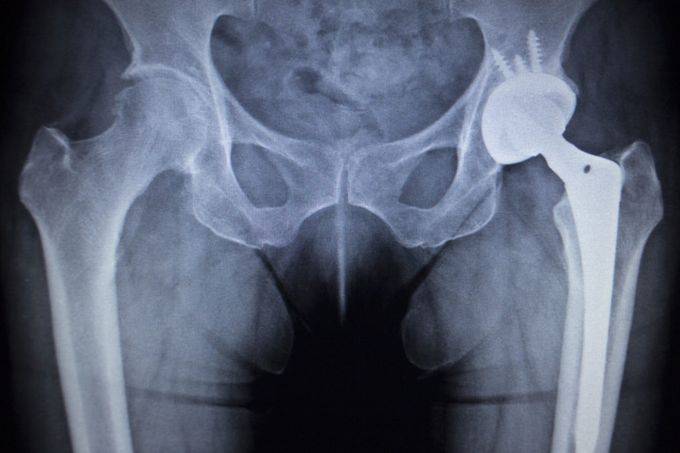

纪录片通过大量真实案例与深度访谈,将医疗设备行业 “急速追求创新” 的弊端直观呈现。片中详细展示了部分企业为抢占市场、追求利益,在设备安全性与有效性尚未经过充分验证的情况下,便急于推动产品上市;而不够完善的监管体系,又难以对这些行为形成有效约束,导致问题设备流入临床后,给患者的健康埋下巨大隐患。那些因使用问题医疗设备而遭遇健康危机的患者,他们的亲身经历与痛苦倾诉,让观众深刻感受到 “技术失控” 对个体命运的沉重打击,也让 “医疗创新” 不再是单纯的正面标签,而是与 “责任”“安全” 紧密相连的复杂议题。